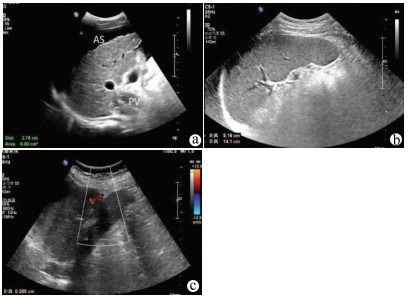

肝病超声诊断指南

中华医学会超声医学分会, 中国研究型医院学会肿瘤介入专业委员会, 国家卫生和健康委员会能力建设和继续教育中心超声医学专家委员会

2021, 37(8): 1770-1785. DOI: 10.3969/j.issn.1001-5256.2021.08.007

摘要(3068) HTML (6587) PDF (9311KB)(804)

超声检查无创、实时、价廉,无辐射、便于反复进行,是最常用的肝脏影像学检查方法。近年来,超声检查新技术如超声造影、弹性成像发展迅速,可有效鉴别肝内占位性病变性质、评估肝纤维化和门静脉高压程度以及监测肝病治疗效果,在临床肝病及其介入治疗中发挥重要诊断价值。本指南规范了肝病多模态超声技术(灰阶超声、彩色多普勒超声、超声造影、弹性超声)检查的仪器调置、患者准备及医生检查方法;对肝脏弥漫性病变(炎性病变、纤维化、硬化)、多种占位性病变及肝病介入操作的多模态超声技术诊断标准进行了定义和规范,同时推荐了超声监测周期及肝脏疾病超声诊断报告书写规范。